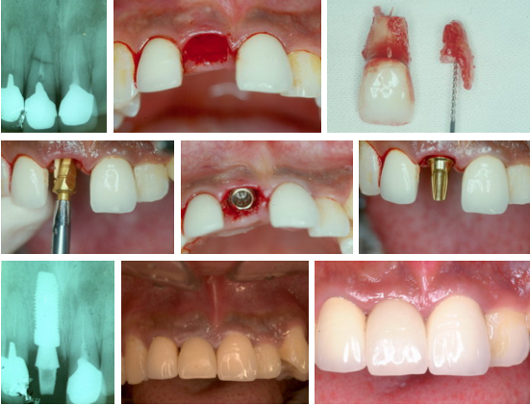

임플란트 단일치아 보철물 : 하나의 임플란트를 식립하여 하나의 치아를 수복합니다.

임플란트 치료는 크게 수술 단계와 보철 단계로 나누어집니다.

수술 단계는 뼈 안에 임플란트를 식립하는 과정입니다. 수술 규모가 작으면 부분마취만으로 수술하며, 규모가 클 경우 전신마취 하에 수술하기도 합니다.

수술 후에는 임플란트가 뼈와 잘 붙어 고정되도록 기다리는 치유 기간이 필요합니다. 얼마나 기다려야 하는가는 경우마다 다릅니다. 수술 직후부터 임플란트가 뼈와 단단히 고정되어 있고 기타 여건이 좋을 경우에는 치유 기간을 생략하고 곧바로 보철 단계로 진행할 수도 있는 반면, 잘 고정되지 않았을 경우 뼈가 자라나 잘 고정되도록 수 주일에서 수 개월의 치유기간이 필요하게 됩니다. 뼈가 부족하여 골이식을 함께 행한 경우에는 추가로 치유 기간이 더 필요할 수 있습니다. 치유 기간 동안 치유 상태의 확인을 위해 1-2개월에 1회 정도의 내원이 필요합니다.

보철 단계는 식립된 임플란트 위에 치아 구조물을 올리는 과정입니다. 임플란트가 뼈와 잘 고정되었다고 판단된 이후에 진행합니다. 치료 규모에 따라 차이가 있을 수 있으나, 대략 1주 1회의 내원을 기준으로 1-2개월의 기간이 필요합니다.